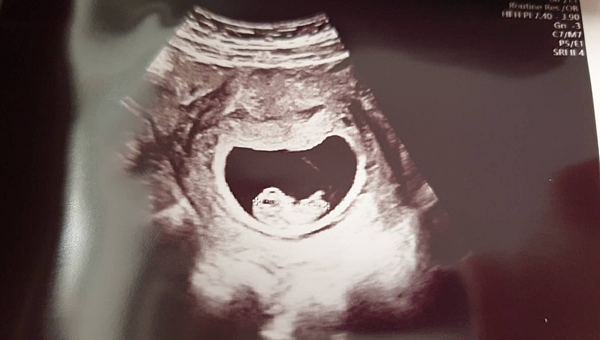

▌第一次產檢(4周) 終於看到小小的胚胎了 ▌

因為一開始在一般婦產科 只有驗孕沒有照到胚胎

所以這還是讓我緊張到不行

隔一周 我立刻就跑到 "板橋菡生婦幼診所"找邱淑芳邱院長報到了

(現在換了新大樓 但邱醫生的門診還是跟七年前一樣人多到爆滿出來阿~)

邱醫師看到我跟小雞毛都超驚喜

直嚷嚷我等你們等好久 終於盼到了(笑)![]()

然後馬上熟練的把我拉近診療室開始看診

本來算一算時間 邱醫師也沒把握能照到胚胎

沒想到還真的找到了![]()

至少有乖乖落在子宮裡 就讓我心裡大石頭落下了